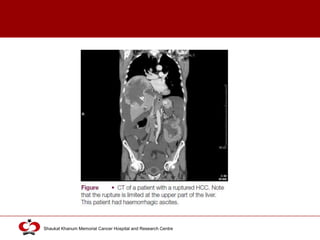

Spontaneous Rupture • 5-15 % cases

• Superficial or protruding tumors

• Suspect:

• Known HCC/cirrhosis + acute epigastric pain or

• Asian/African men with acute abdomen

• Minor rupture:

• Abdominal pain

• Hemorrhagic ascites

• Hypovolemic shock (50 % cases)

 Complicated HCC (ruptured)

 Actively treated unless terminal presentation (multiple tumors, PVT and

end stage liver disease)

 Primary aim of treatment: Stop bleeding (arterial embolization)

 Subsequent hepatectomy (long term survival)

 Source of bleed:

 Tumor rupture

 Rupture of artery at junction of tumor and adjacent parenchyma

 Rupture not always associated with peritoneal seeding of tumor cells